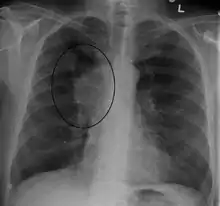

Діагностика

Основними методиками діагностики СВПВ є рентгенографія органів грудної клітки, КТ, трансбронхіальна аспірація під час бронхоскопії та медіастиноскопія.[8] Рентген часто дає можливість побачити основну причину СВПВ. Однак 16 % людей із СВПВ мають нормальний рентген грудної клітки. КТ слід посилити контрастом і робити на шиї, грудях, нижній частині живота та тазі. Вони також можуть показати основну причину та ступінь прогресування захворювання.